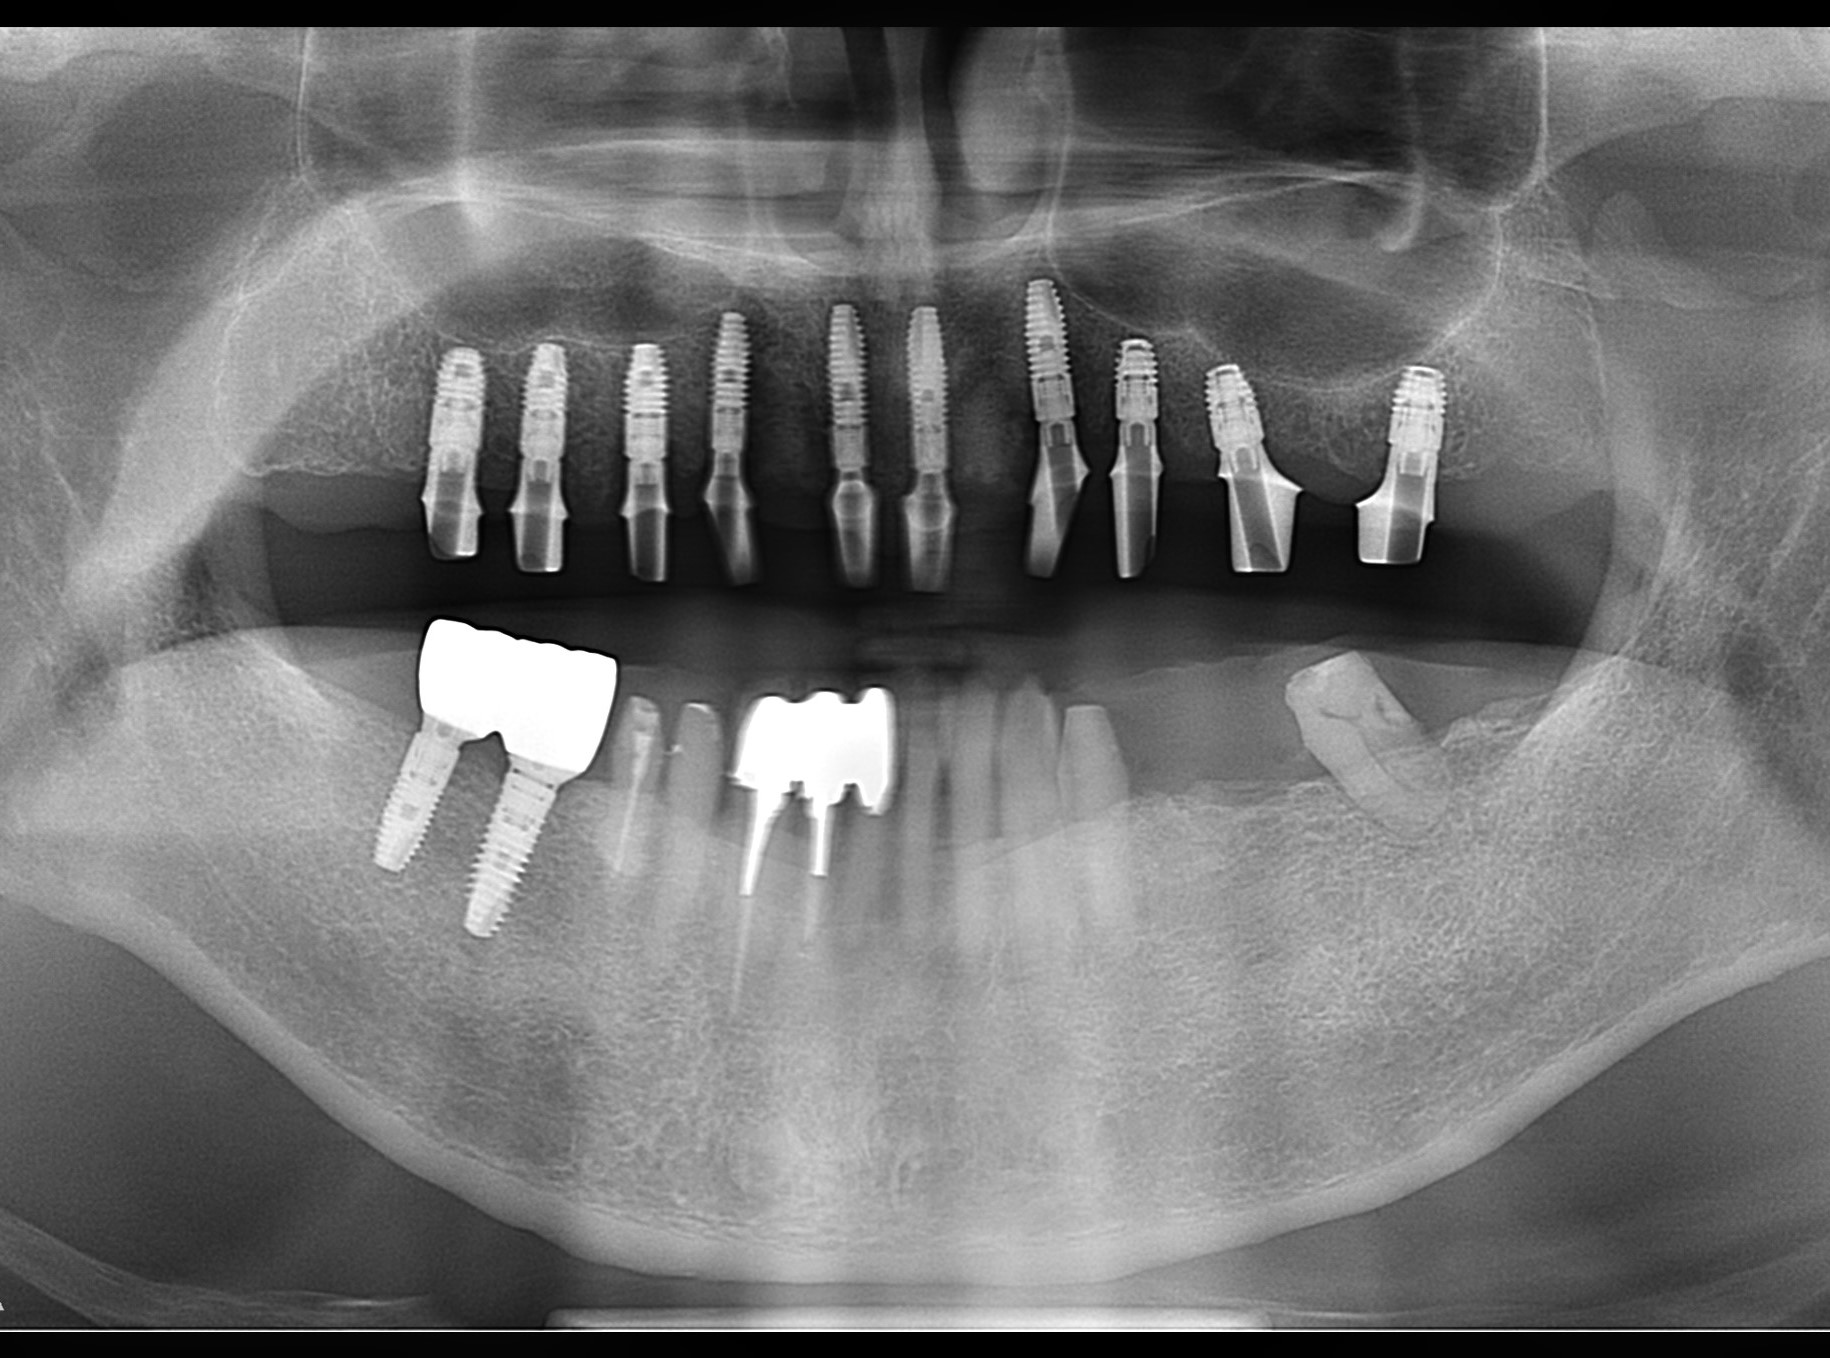

この患者さんは、総入れ歯ではなく、固定式のボーンアンカードブリッジを希望され、昨年末に1回の手術で10本のインプラントを埋入しました。

P6.pano